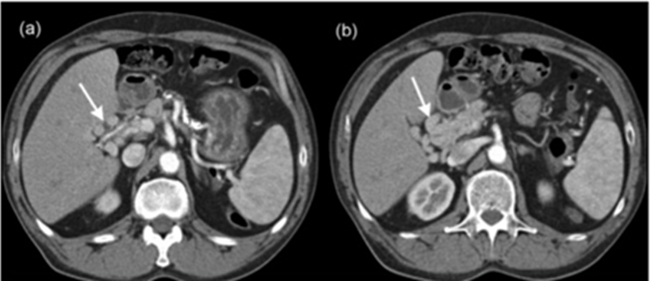

Thrombosis of portal vein is a result of local and systemic factors.1 When the symptoms occur sixty days before presentation, PVT is therefore considered acute, it presents with acute symptoms such as fever, abdominal pain and vomiting.7 When PVT reaches a chronic stage, it is associated with formation of collateral veins and is therefore called “portal cavernoma” (Figures 1-5).8 The diagnosis of PVT involves Doppler ultrasonography, MRI, CT that are considered non-invasive methods, they have replaced invasive tests of portal vein.9

Figure 4A, B Abdomen tomography showing acute portal thrombosis and chronic portal thrombosis with portal cavernoma.1,9